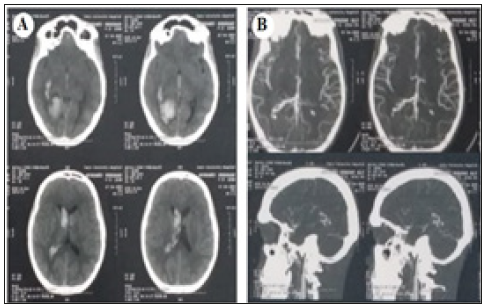

A 33 years old male without a medical history presented with sudden onset of severe agonizing occipital headache, followed by nausea, vomiting and blurring of vision. By examination, the patient was conscious, with neck rigidity and bilateral grade-I papilledema mRS 1. Non-contrast CT brain was done and showed right occipital horn hematoma with extension to the 3rd ventricle and both anterior horns. CT angiography shows small AVM in the right occipital region (Figure 5).

Figure 5:(A) CT brain shows R.t occipital horn hematoma extending to body of R.t lateral ventricular body, both anterior horns of lateral ventricle and third ventricle. (B) CT angiography shows small AVM in the R.t occipital horn.

Follow-up diagnostic catheter was done 3 months later and shows complete curative occlusion of the nidus. The mRS of the patient is now zero (Figure 9).